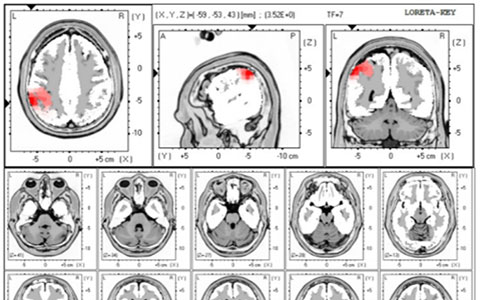

LORETA/sLoreta

Resting State Brain Connectivity Analyses & Imaging